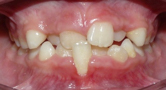

5 MORDIDA CRUZADA ANTERIOR

Cuando los incisivos superiores muerden por detrás de los inferiores.